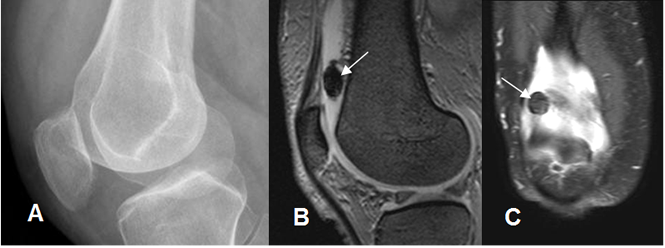

Fig 193. Condromatosis sinovial.

A: Rx oblicua. No se encuentran anormalidades.

B: RM sagital en FFE y C: RM coronal en STIR. Moderado derrame articular, con cuerpo

libre no calcificado en el espacio suprapatelar.